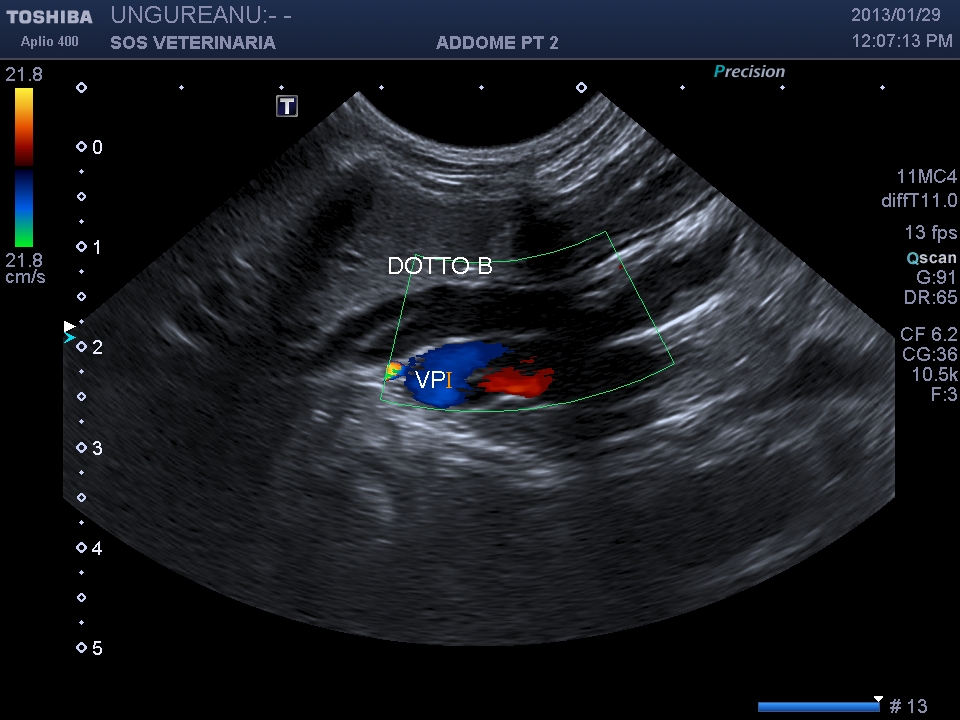

Le vie biliari del gatto hanno caratteristiche diverse rispetto al cane il dotto pancreatico principale raggiunge il coledoco  prima che questo defluisca nella papilla duodenale maggiore (nel cane lo sbocco e’ indipendente) ,inoltre il dotto accessorio  sfocia nella papilla minore ,un processo ostruttivo distale porta quindi a distensione  di entrambe le componenti  ,l’iperplasia della parete delle vie biliari  puo’ essere indicativa di flogosi o di cronicita’ dell’ostruzione  (in questo caso la parete e’ normale) ma come sopraesposto la diagnosi richiede spesso invasivita’ ,questo caso purtroppo  non ha seguito nessuna diagnosi ,il soggetto non ha risposto alla terapia cortisonica (l’unica che ha voluto tentare il proprietario) e antibiotica e si e’ perso nel foll’up, Una laparotomia esplorativa con campionamento del tessuto iperplastico  e coltura biliare era a mio avviso unica opzione possibile per una corretta diagnosi .

Il caso si mostra interessante sul piano dell’imaging che evidenzia la complessita’ delle vie biliari extraepatiche e pancreatiche dilatate.